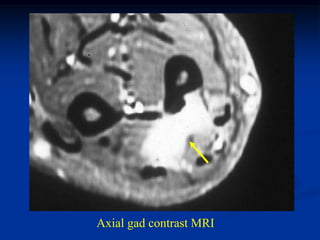

Case #1184.1              Lipoma               CT scan

51 year old male with soft painless mass in buttocks for 5 yrs

Axial T-1     T-2

Gad

Cor T-1         T-2

Sag gad

Case #1184.1 Lipoma CT scan 51 year old male with soft painless mass in buttocks for 5 yrs

• 50.

Axial T-1 T-2 Gad

• 51.

Cor T-1 T-2 Gad

• 52.

• 53.